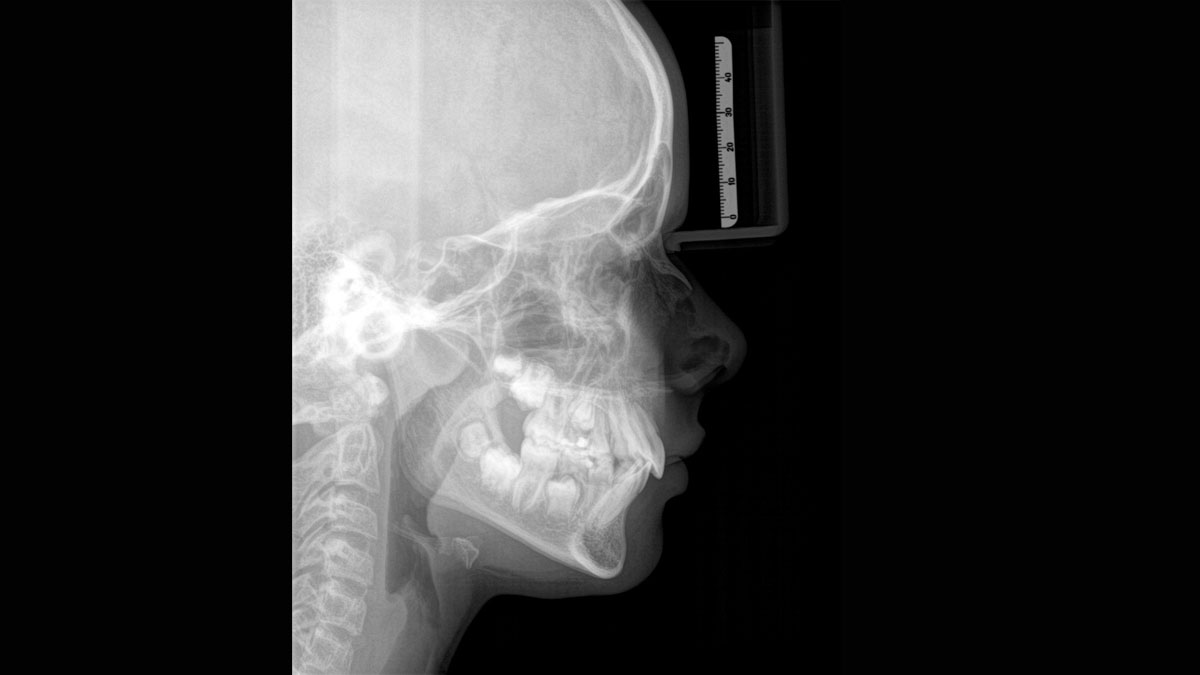

For exceptional panoramic images with high sharpness. You can choose an optional right or left cephalometric arm, which can be retrofitted at any time

When trying to capture a successful medical or dental X-ray there is an ongoing fundamental conflict. On the one hand, you want to do whatever it takes to acheive maximum image quality, on the other hand, the radiation dose should be as low as reasonably achievable for the patient. At Dentsply Sirona we are dedicated to offering products that ensure exceptional image quality while supporting safe and ethical practice. When developing our products, we observe the internationally valid ALARA principle (as low as reasonably achievable).

Thanks to the optimised low dose mode with a dedicated filter, the imaging of dense structures, such as bones, is possible at a greatly reduced dose. This makes Intelligent Low Dose an attractive and efficient option for many clinical situations. Whether in orthodontics or implantology - with Dentsply Sirona solutions you will find the optimum setting for every case.